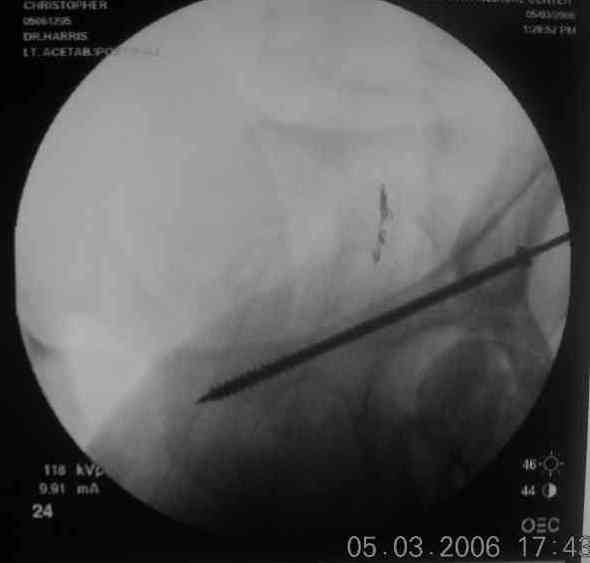

The 2nd example is of a motorcyclist with a transverse fracture-dislocation...he had a closed attempted reduction and placed in traction but the manipulative reduction was not concentric (not unusual for this injury pattern)...so the traction was adjusted to be just enough to disengage the head from the fracture (12#) until he could be cleared for surgery one day after injury...he was treated "urgently" then with a prone KL, clean the fracture, reduce and clamp it, screw it, support with a balanced plate, close, and enjoy...2-3hours, 400cc EBL, blah, blah, blah..

Here's a pic from the foot of the bed and you can see the clamp in the wound and the knee is extended so he must've had a tight rectus. The C-arm is rolled back to an obturator oblique image to reveal the anterior column...we put a slight outlet tilt to combine the images and give a better view of the anterior column...we can see the posterior column limb reduction in the wound, we can palpate the quadrilateral surface limb, and the image demonstrates the anterior column portion...you can adjust the tilt and rotation to image tangentially to the fracture plane if you'd like. We've inserted a 2mm K wire to site the starting point and aim/orientation for the drill and screw

Prone Imaging

Prone Inlet

OK, now we're inserting the drill percutaneosuy using a sleeve. This fluoro shot is not for this patient (notice no clamp) but I was too lazy to go searching the PACS for one with the clamp on, so pretend...I'll save the next ones and send along...the imaging is the same and the clamp doesn't obstruct imaging other than very rarely...you can always tilt the C-arm a bit to clear it if the clamp obstructs the exact spot that you'd like to see. We'll assume that everyone knows the safe zone for a medullary ramus screw. Use a calibrated drill and sleeve of known length to simplify your life...or use Alex's fancy cannulated screws...I like 3.5mm screws because the oscillating 2.5mm drill bounces and remains intraosseus when it oscillates and contacts endosteal cortical ramus... so will the screw, and like a long bent screw IF the fracture is clamped... if unclamped, when the screw contacts the endosteum, it pushes the reduction apart instead of bouncing. The big 7mm cannulated screws fit few patients and extrude...we very rarely use them any more...you'll see an old one later.

Prone Obturator-Outlet

Screw insertion using the obturator-outlet combination image.